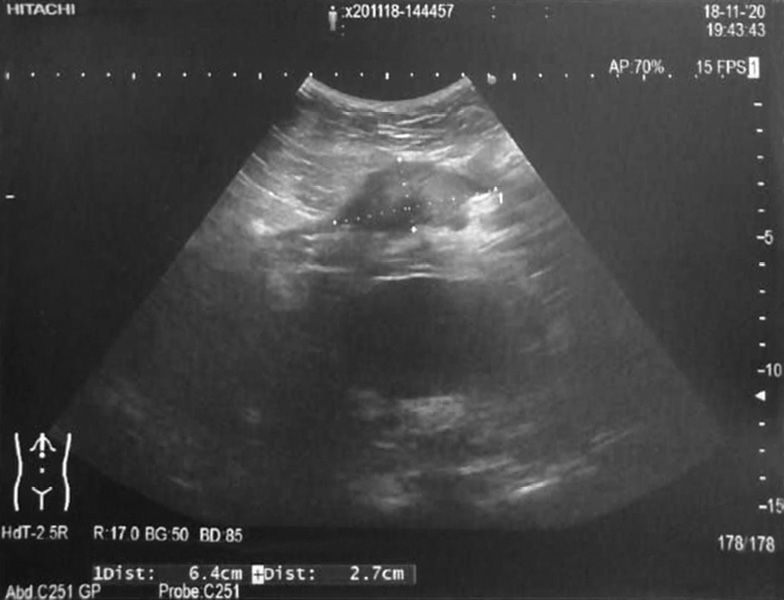

In all cases, for diagnostics at the preoperative stage, US findings of the soft tissues of the anterior abdominal wall in the scar area were used. US detected lesions of various sizes with uneven contours and heterogeneous echostructure with hypo- and hyperechoic inclusions (Fig. 2). In three cases, a fine-needle puncture biopsy of the lesion under US control was performed. Cytological examination of puncture samples revealed accumulations of cells of the glandular epithelium of the endometrial type and large amounts of hemosiderin.

Fig. 2. Ultrasound examination of the soft tissues of the anterior abdominal wall in postoperative scar endometriosis

Рис. 2. Ультразвуковое исследование мягких тканей передней брюшной стенки при эндометриозе послеоперационного рубца